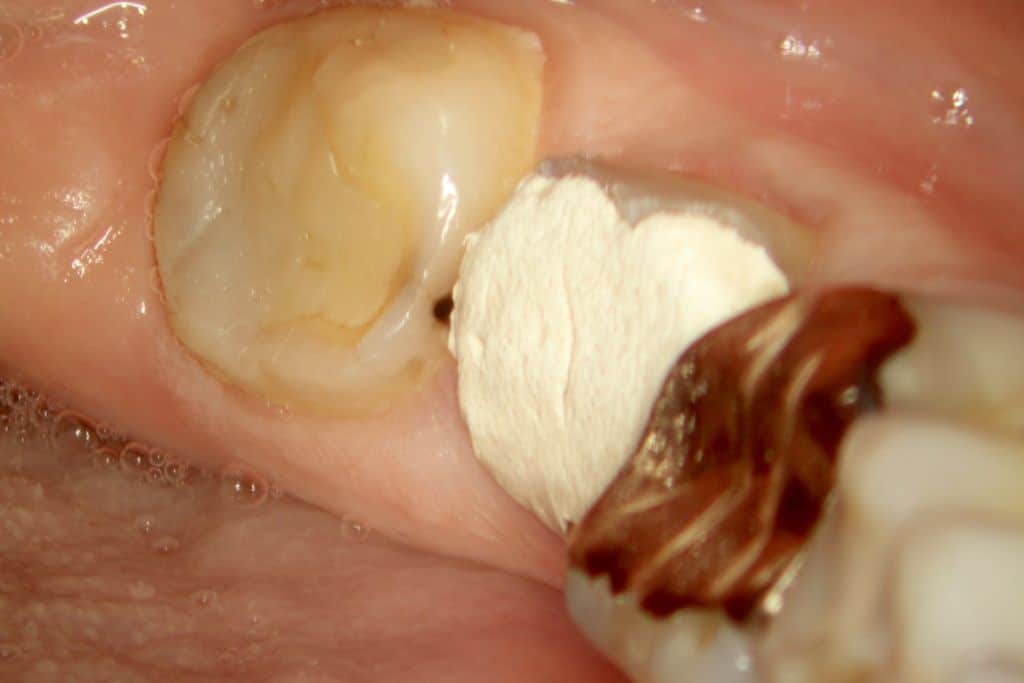

- Figura 2 – Condição clínica inicial.

Paciente do gênero feminino, 56 anos de idade e caucasiana compareceu ao consultório se queixando de dor espontânea, pulsátil, que não cessava com o uso de analgésicos e anti-inflamatórios na região de mandíbula esquerda. Apresentou resposta negativa para o teste de palpação apical e percussão vertical e lateral em todos os dentes do referido quadrante. Aos testes térmicos apresentou resposta positiva exacerbada e de longa duração tanto ao frio quanto ao calor apenas no dente 37. Nos outros dentes do quadrante apresentou resposta positiva leve e de curta duração ao frio e negativa ao calor.